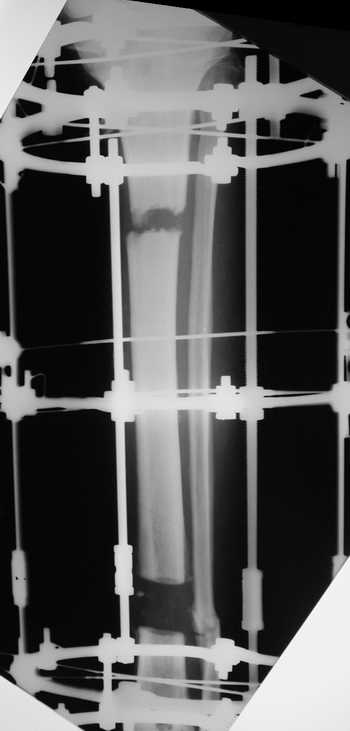

Адаптация отломков гексаподом за 5 дней (рис 5). Замена гексапода на обычные штанги (рис 6 и 7)